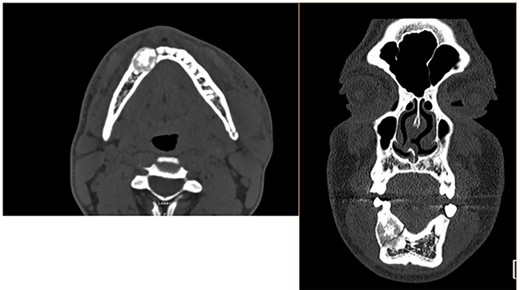

We present a case of a 20-year-old African American male with medical history of asthma who presents for evaluation of facial trauma. Patient was involved in an altercation sustaining direct trauma to the mandible and presented to the emergency department for evaluation of jaw pain. Prior to the altercation, patient denied dental, facial or neck mass issues. On clinical exam, he had tenderness and swelling over the left angle of the mandible as well as right mandibular parasymphysis. Tooth #25 was slightly mobile otherwise all other dentition was intact. He underwent computer tomography (CT) scan of the facial bones, which showed a non-displaced left mandibular angle fracture, a non-displaced right mandibular parasymphyseal fracture extending through a 2.3 cm expansile well-defined partially sclerotic lesion, as shown in Fig. 1. The lesion was core biopsied resulting as an ossifying fibroma. The patient was offered segmental resection with reconstructive options of osseous flap. The patient refused free flap reconstruction and elected for resection with plating technique. The patient then underwent segmental mandibulectomy of the tumor with large titanium plate reconstruction as well as open reduction internal fixation of the left mandibular angle fracture, as shown in Fig. 2. The final pathology resulted as central ossifying fibroma. The patient healed well without post-operative complications.

CT scan of the facial bones. These CT images in the axial (left) and coronal (right) view depict the 2.3 cm mandibular mass with pathologic fracture on the medial aspect as well as a non-displaced left mandibular angle fracture.